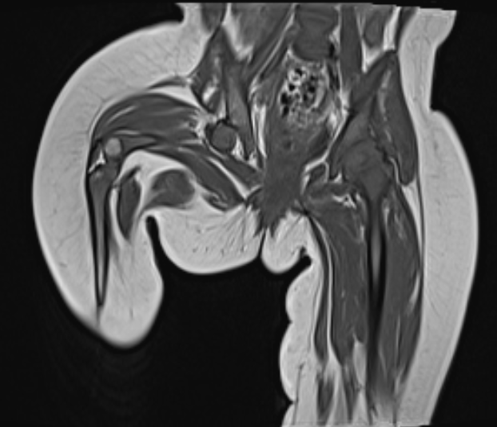

• A well defined extra-axial T1 and T2 hyperintense lesion measuring 4.1 x 2.7 cm is seen anterior to the right temporal lobe mildly effacing the right anterior temporal lobe.

• Along the posterolateral aspect on  right side there extension of the contents into the subdural space forming a large subdural collection.

• A large late subacute subdural haemorrhage is seen along the entire right cerebral convexity with maximum thickness measuring 2.1 cm is seen.

• Mass effect is seen in the form of locoregional sulcal effacement and compression of right lateral and third ventricles with midline shift to the left measuring 1.3 cm.

• A well defined extra-axial T1 and T2 hyperintense lesion anterior to the right temporal lobe with extension into the subdural space forming a large subdural collection.

• A large late subacute subdural haemorrhage is seen along the entire right cerebral convexity with mass effect and midline shift as described.

Features likely to represent right anterior temporal extra axial  arachnoid cyst with rupture and associated right cerebral convexity subdural hemorrhage as described above.